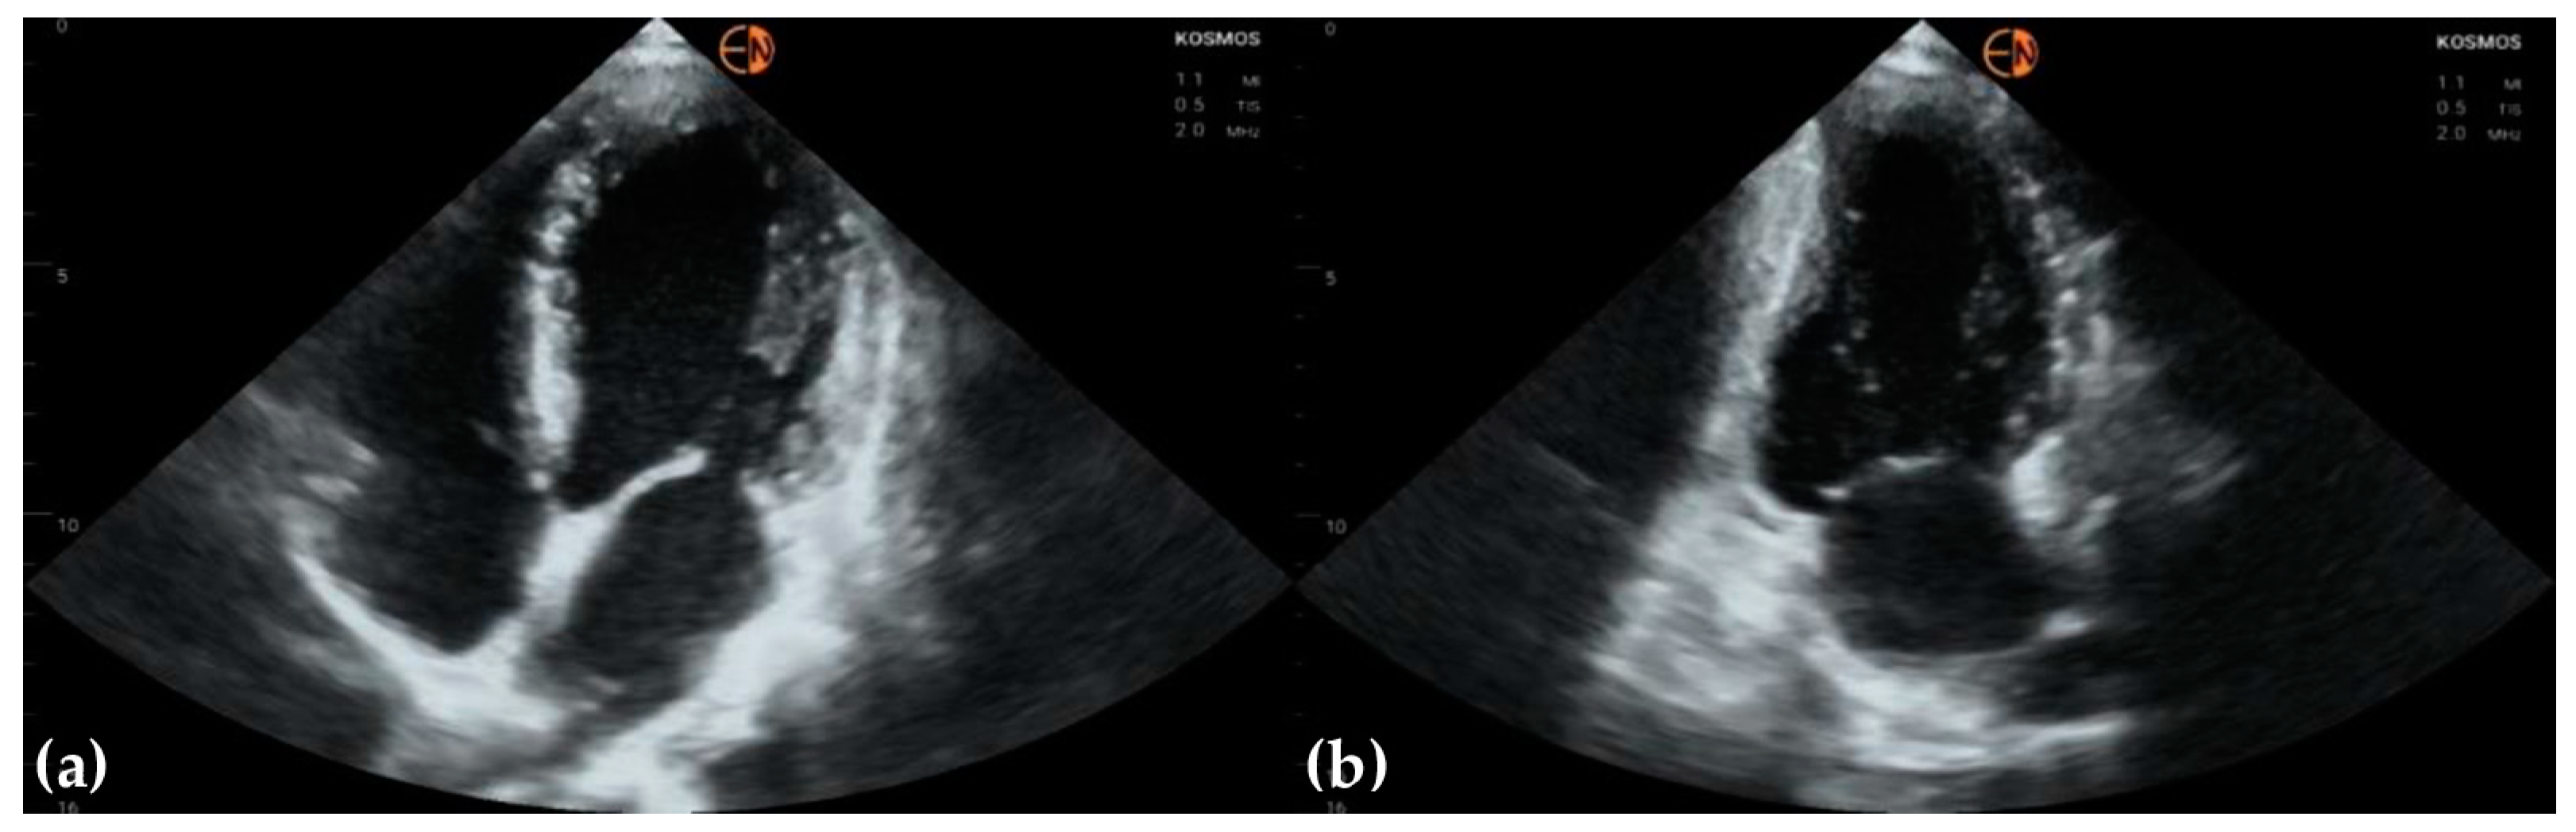

3.4. Other Findings

| Aortic valve | 33 (78.6 [62.8 to 89.2]) 0.6557 [0.3862 to 0.9252] | ||

| Mild aortic regurgitation | 10 | 5 | |

| Moderate aortic regurgitation | 1 | 0 | |

| Mild aortic stenosis | 1 | 1 | |

| Severe aortic stenosis | 1 | 1 | |

| Normal | 29 | 35 | |